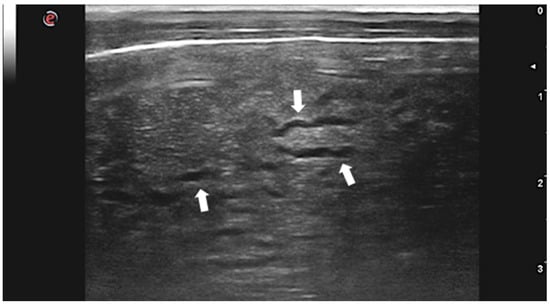

- Moshnikova, V.S.; Gilmour, L.J.; Cook, A.K.; Fabiani, M. Sonographic findings of pinpoint hyperechoic foci in the small intestine, liver, and mesenteric lymph nodes are indicative of canine Heterobilharzia americana infection. Vet. Radiol. Ultrasound 2020, 61, 583–591. [Google Scholar] [CrossRef]